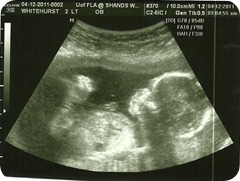

But until then here are some pictures and the stats of our Trio! Just as a side note they are already very rambunctious kicking each other in the womb during the ultrasound!

Group shots: They no longer ALL completely fit in the frame.

Baby 1’s head in lower right corner. Baby 2’s legs or feet depending on pic. in upper middle. Baby 3’s head in far left.